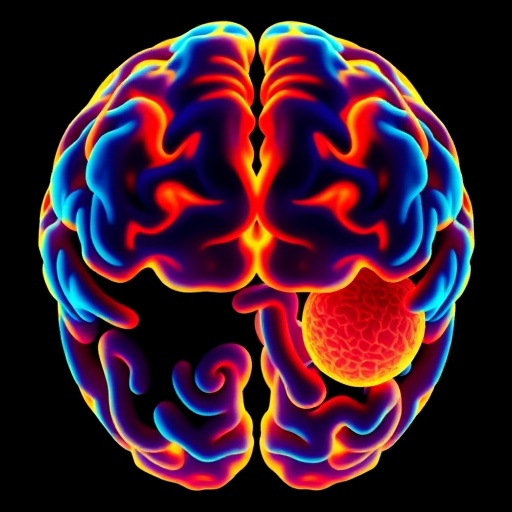

Brain scans of more than 1200 HIV-infected adults across 5 continents show smaller volumes associated with lower white blood cell counts

Credit: Image courtesy of Talia M. Nir, Neda Jahanshad, and James Stanis of the Mark and Mary Stevens Neuroimaging and Informatics Institute at the Keck School of Medicine of USC.

The researchers looked at the link between blood plasma, which is routinely collected to monitor immune function and treatment response, and the volume of various structures in the brain. Lower white blood cell counts generally indicate that the immune system is being suppressed. Here, they found, for example, that participants with lower white blood cell counts also had less brain volume in the hippocampus and thalamus, parts of the brain’s limbic system involved in regulating memory, emotion and behavior.

Accelerated atrophy of the hippocampus, the region that showed the most consistent effects in the study, is a hallmark of neurodegenerative diseases such as Alzheimer’s disease. Common age and HIV-related pathological processes, such as inflammation and blood brain barrier impairment, may accelerate age-related neurodegenerative processes.